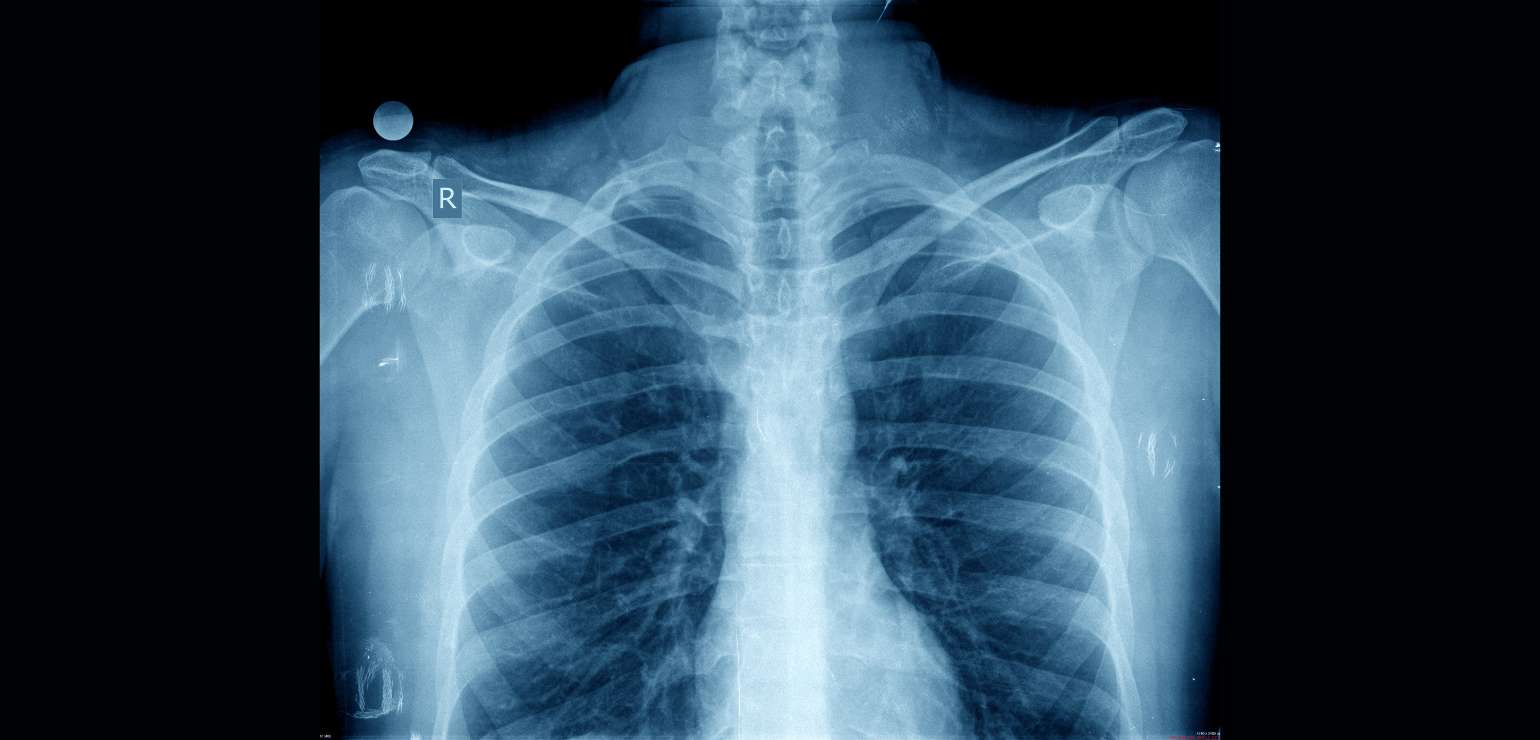

When it is about quality diagnostics and accuracy, specialists look no further than Medcare Diagnostics. Led by internationally trained doctors who have served in the top hospitals of Mumbai, we pride ourselves in the best PET-CT scan and gamma scan facilities. We provide detailed reports, high-end technology which improves patients safety and gives a hassle-free patient experience.

Specialist in Imaging Diagnostics and Nuclear Medicine – CT scan, PET-CT scan, Nuclear Medicine/ Gamma scans and more.